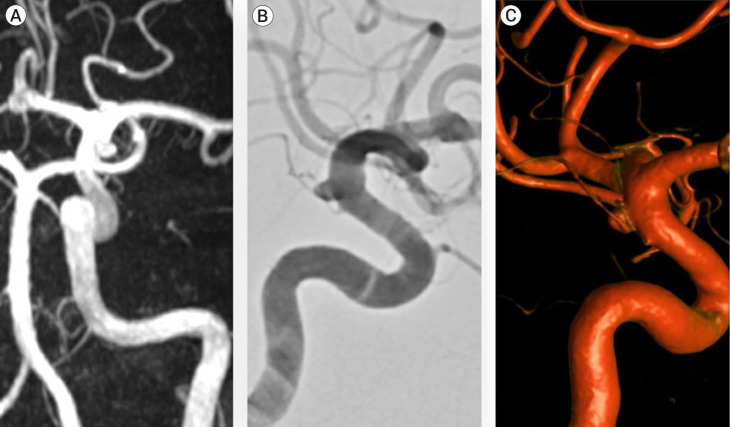

Methods: Retrospective review of prospective surveillance of 420 CI was undertaken in a single tertiary cerebrovascular centre. All CI diagnosed by a neuroradiologist, diagnosed on either a Magnetic resonance angiography (MRA), Computed tomography angiography (CTA) or Digital subtraction angiography (DSA) were eligible for inclusion. Imaging and demographic characteristics were recorded at baseline. CI growth and aneurysm transformation were the outcomes of interest. Groupwise comparison was conducted via Fischer exact testing. Kaplan Meir curves and Cox proportional hazard ratios were used to assess variables of interest with respect to time on surveillance.

Abstract Image